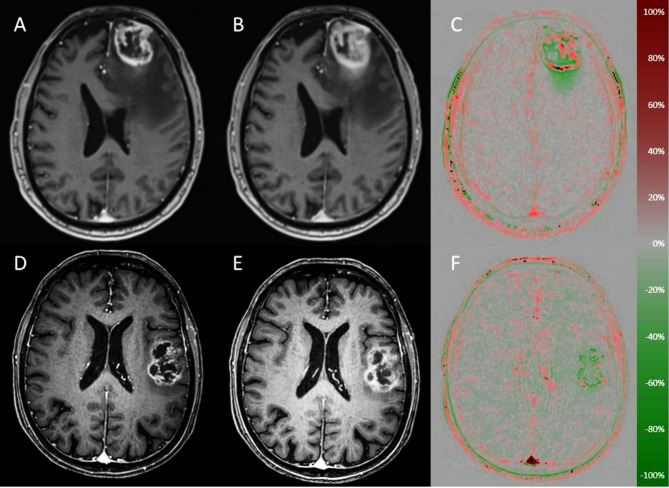

Late enhancement and wash-out maps for differentiation of glioblastoma and metastases.

胶质母细胞瘤和转移瘤分化的晚期增强和消失图。